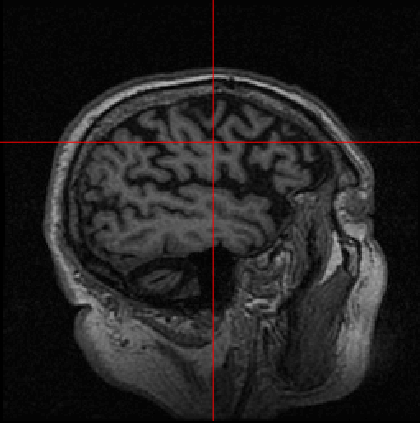

German physicist Alois Alzheimer laid the foundations of most of the modern understanding of the underlying causes of this disorder when he noticed the common biomarkers through histological techniques on the brains of his diseased patients [5]. Recent technologies exist, such as MRI, which helps in visualising atrophy or change in tissue volume of such biomarkers over a period of time, or fMRI, which can identify high-resolution activation of different brain regions during various cognitive tasks [6]. Fig. 1 shows the example of an AD patient’s raw unprocessed brain slice in different planes obtained from MR imaging in a magnetization-prepared rapid gradient-echo (MP-RAGE) sequence.

Refer to caption

(a)

(b)

(c)

Figure 1: MP-RAGE T1 Weighted MR slices: (a) Axial plane (b) Sagittal plane (c) Coronal plane